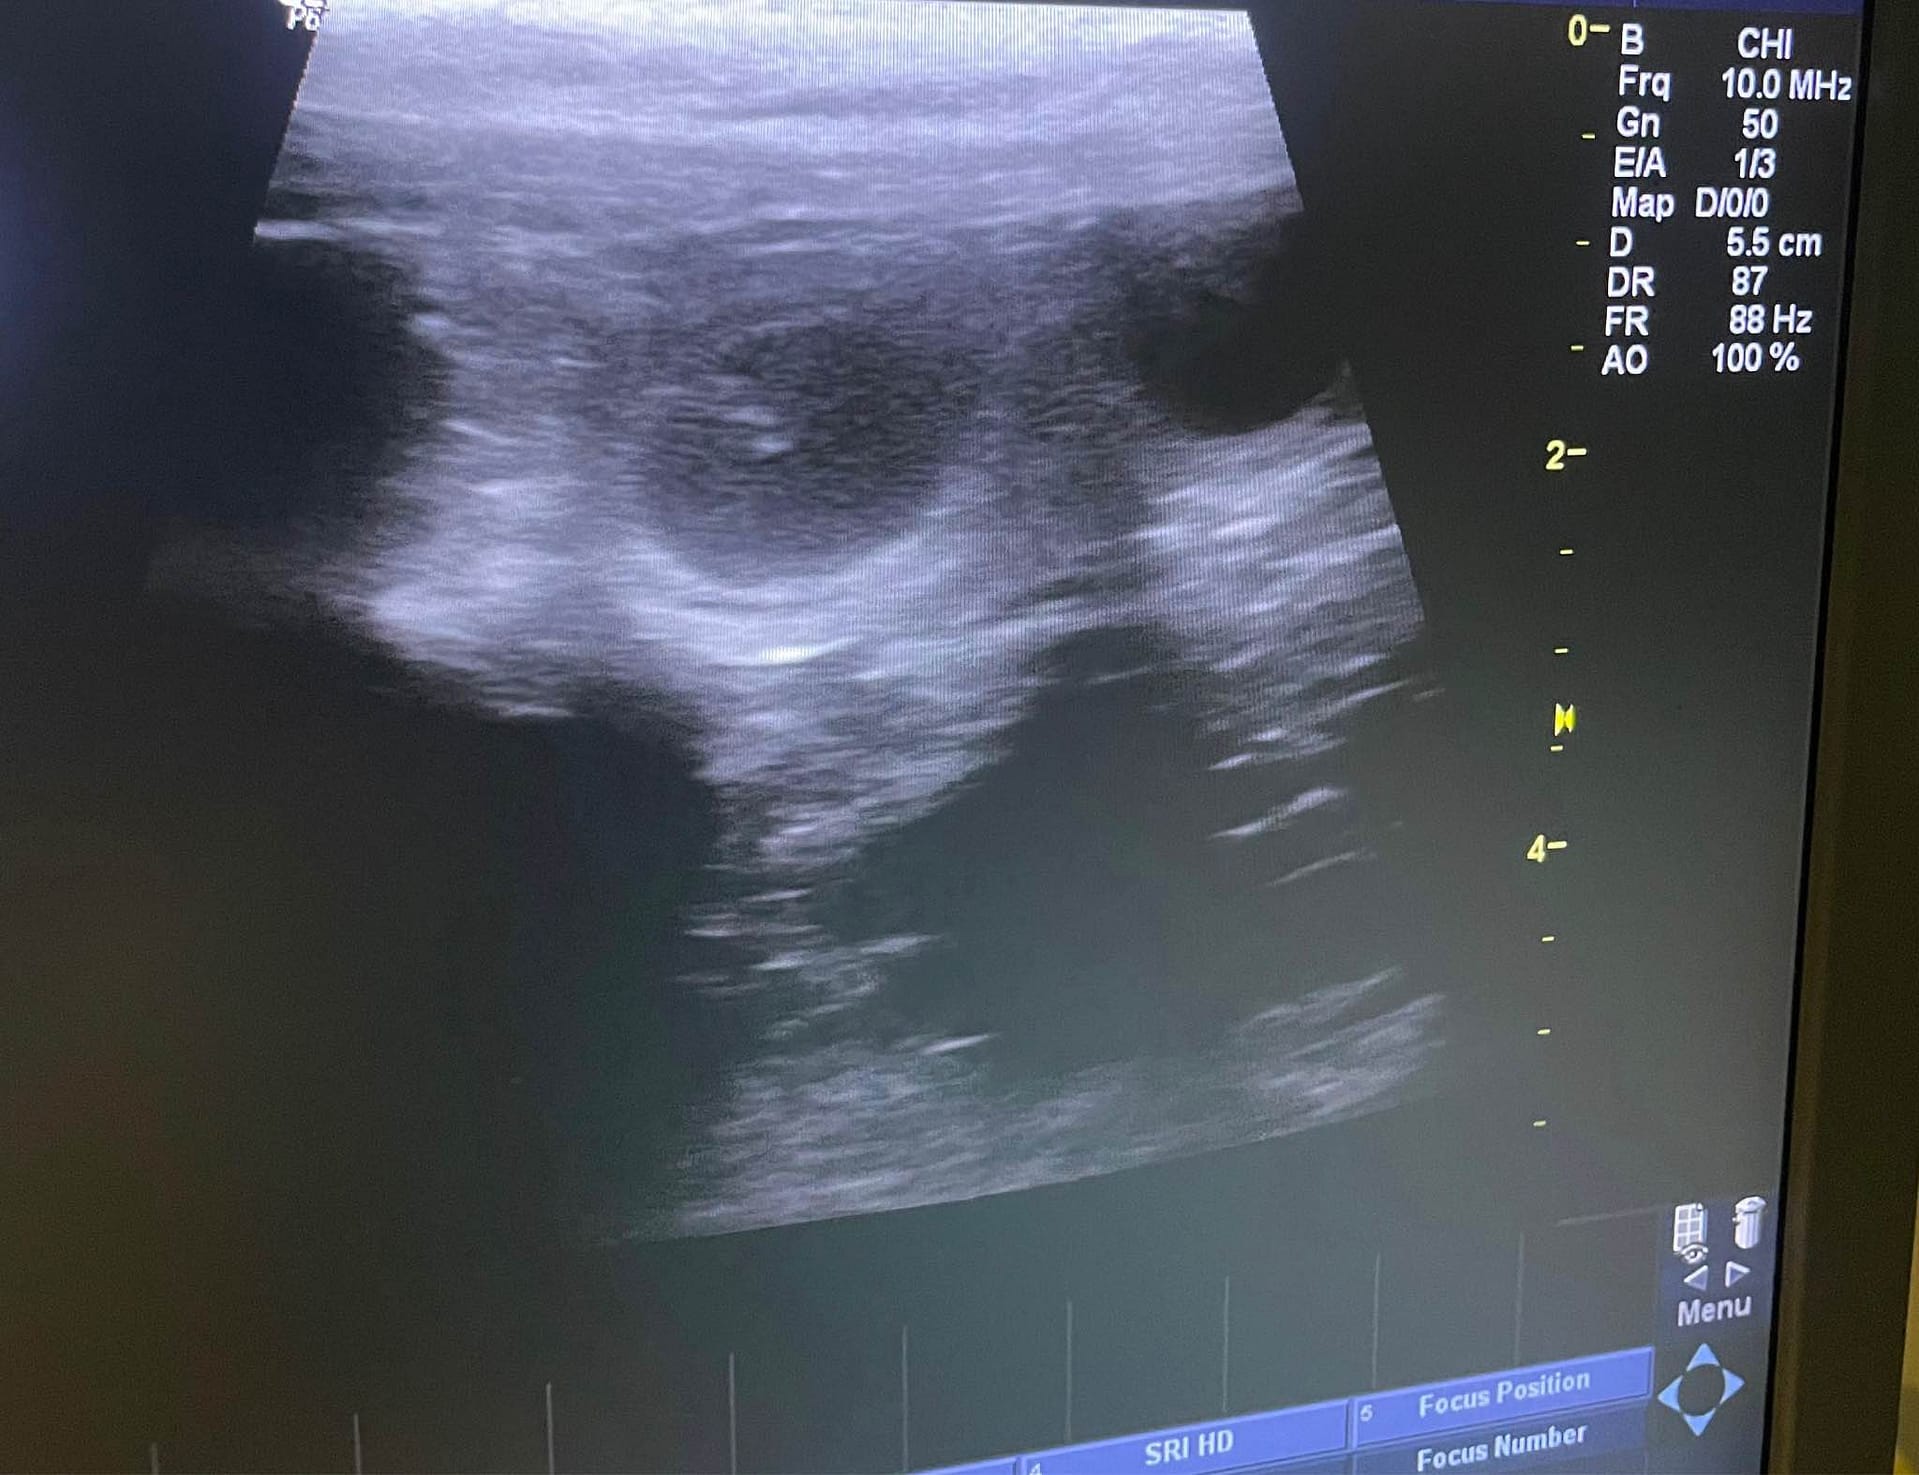

Irma is in whelp! Today she is 23 days post ovulation and embryos are clearly visible. We’ll have count later.

Today we took Irma to Reprovet to check how many puppies there is on board. Irma behaved like good girl and Laura Linntamm confirmed quite a few pups on board! Irma is now on the second trimester and absorbing is still possible. It’s always so exciting to see the final number <3